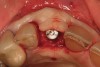

A 46-year-old patient presented with a long-standing fixed partial denture replacing tooth No. 9 (Figure 24). The distal abutment No. 10 was fractured, and the patient was referred for implant reconstruction. During the consultation, the patient expressed a desire to have individual teeth back. Both the periodontist and the restorative dentist recommended a single fixture No. 9 with a cantilevered No. 10 pontic. Due to the bone loss present on the mesial aspect of tooth No. 9 and the bone loss present on the mesial aspect of tooth No. 10, this solution was felt to be the most predictable, using augmentation to build a pontic site for No. 10. Despite extensive consultation, due to the patient’s insistence on single teeth, expectations for an ideal result needed to be managed and the patient accepted therapy understanding that esthetics would most likely be compromised with little chance of complete regeneration (Figure 25 through Figure 33).